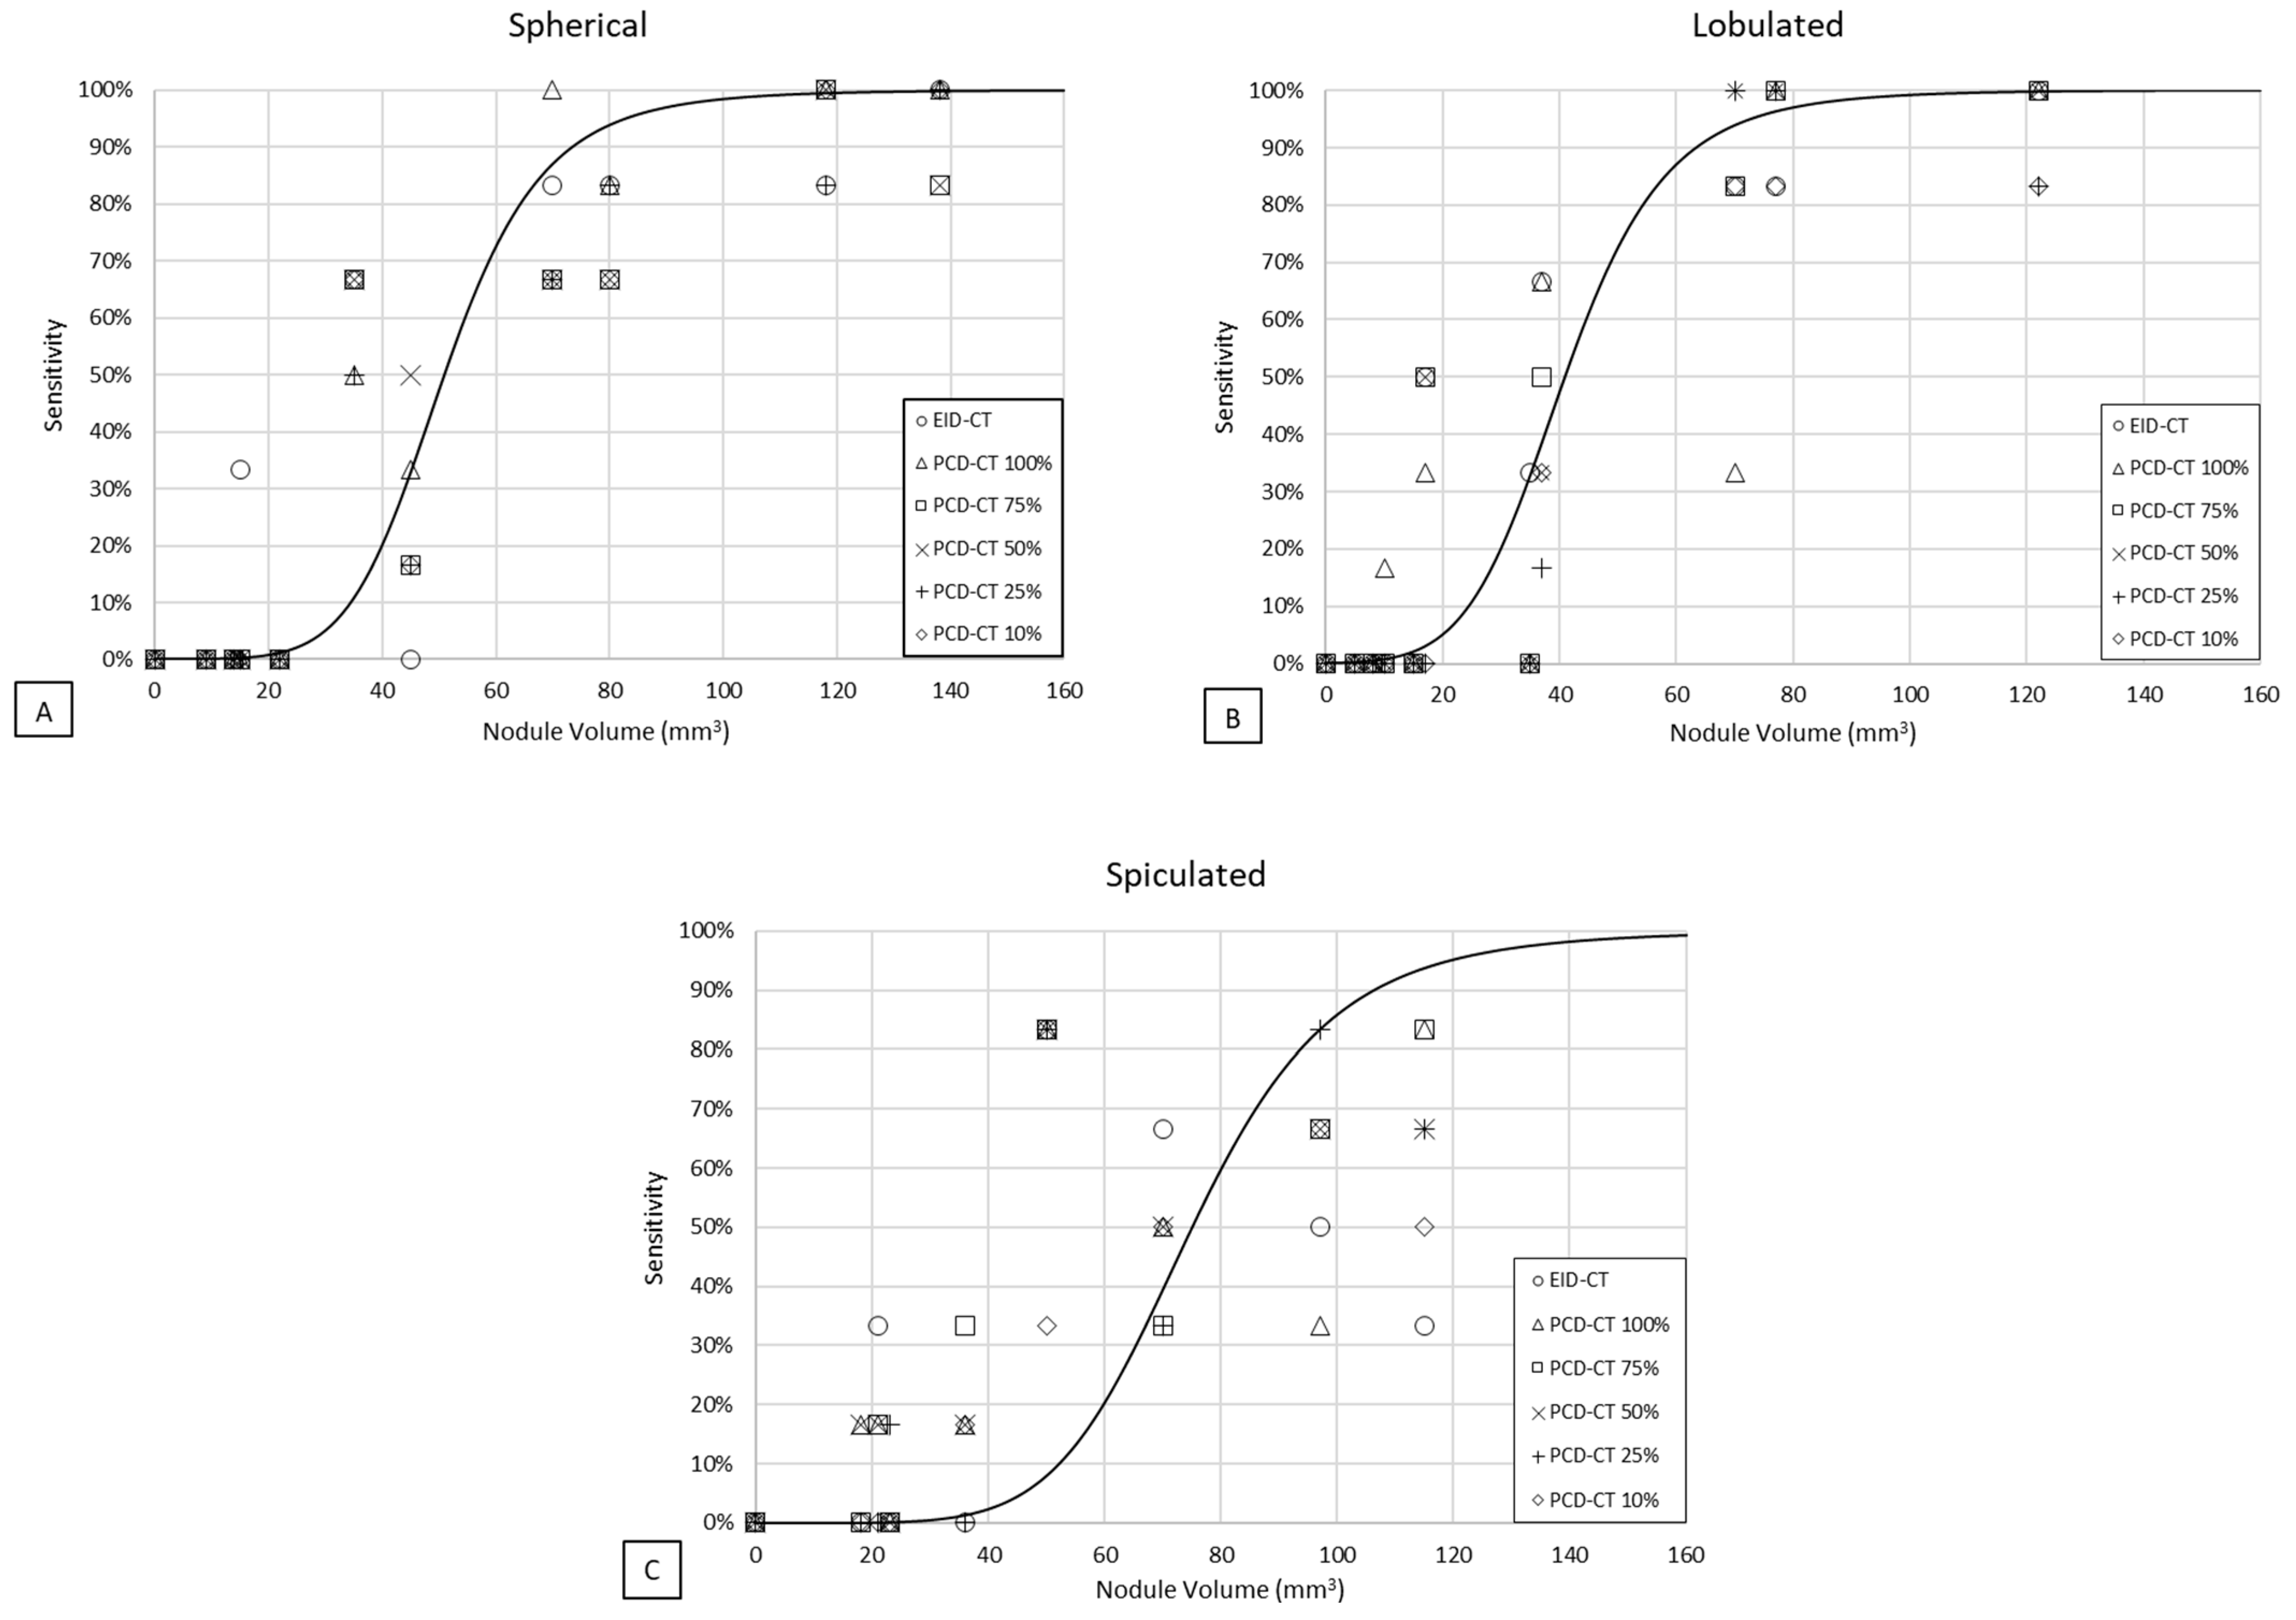

3.1. Detectability

3.2. Volumetric Accuracy